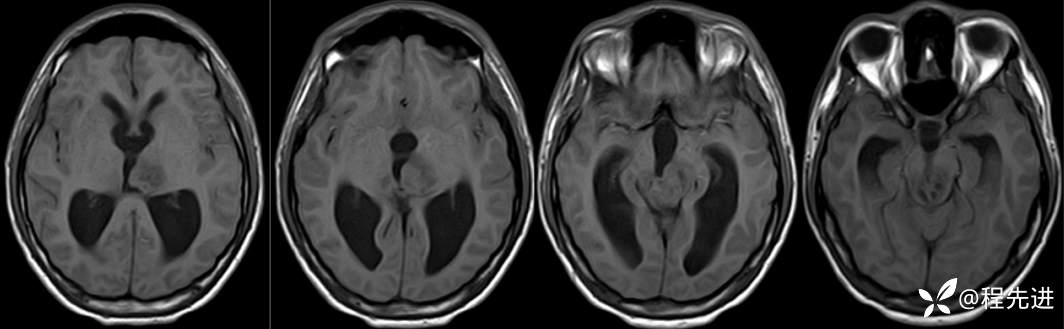

MRI平扫+增强:

T1:

FLAIR: